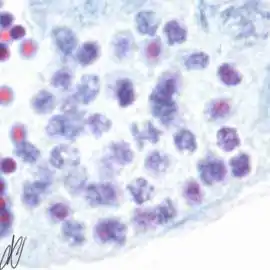

spermatogenesiscysts with successive stages of spermatogenesis in a seminiferous tubule | |||

| H&E | Putt's carbol fuchsin as a marker of spermatogenic maturation |